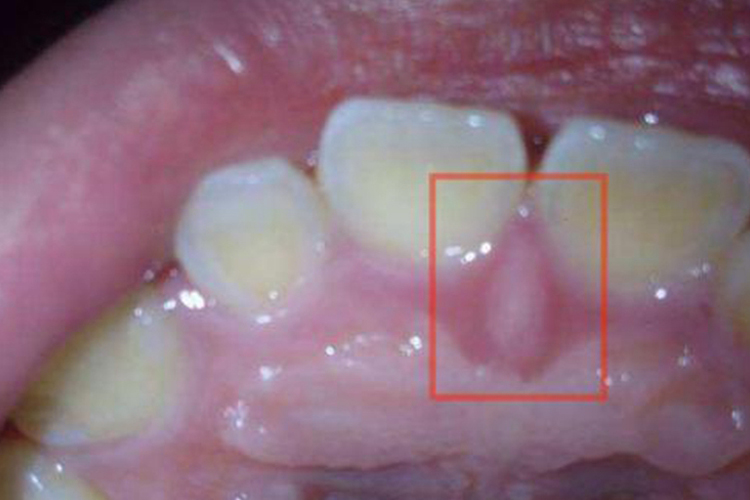

切牙乳头

口腔上颚长肉芽可能是正常的生理结构,即切牙乳头,表现为上颚中缝前端,左右上颌中切牙间的腭侧,有一黏膜隆起,组织致密,其深面为切牙孔,有鼻腭神经、血管经过。